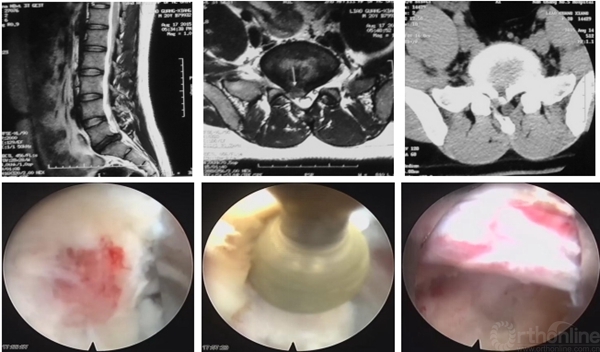

3D-CT:可观察骨性结构狭窄,如椎间孔区域狭窄,此类患者可行脊柱内镜下椎间孔扩大出口神经根减压治疗

3D-MRI:普通MRI无异常,3D-MRI发现游离髓核,行脊柱内镜取出游离髓核

3D-MRI:对一些特殊类型的椎间盘突出(如极外侧腰椎间盘突出)可起到更加准确的诊断作用

介入诊断技术:选择性神经根阻滞技术、椎间盘造影技术等,不仅可以从患者的主观感受进一步精准诊断,同时对脊柱内镜手术的疗效可以起到预测作用。

怀疑融合临近节段极外侧突出,选择性神经根阻滞术明确诊断